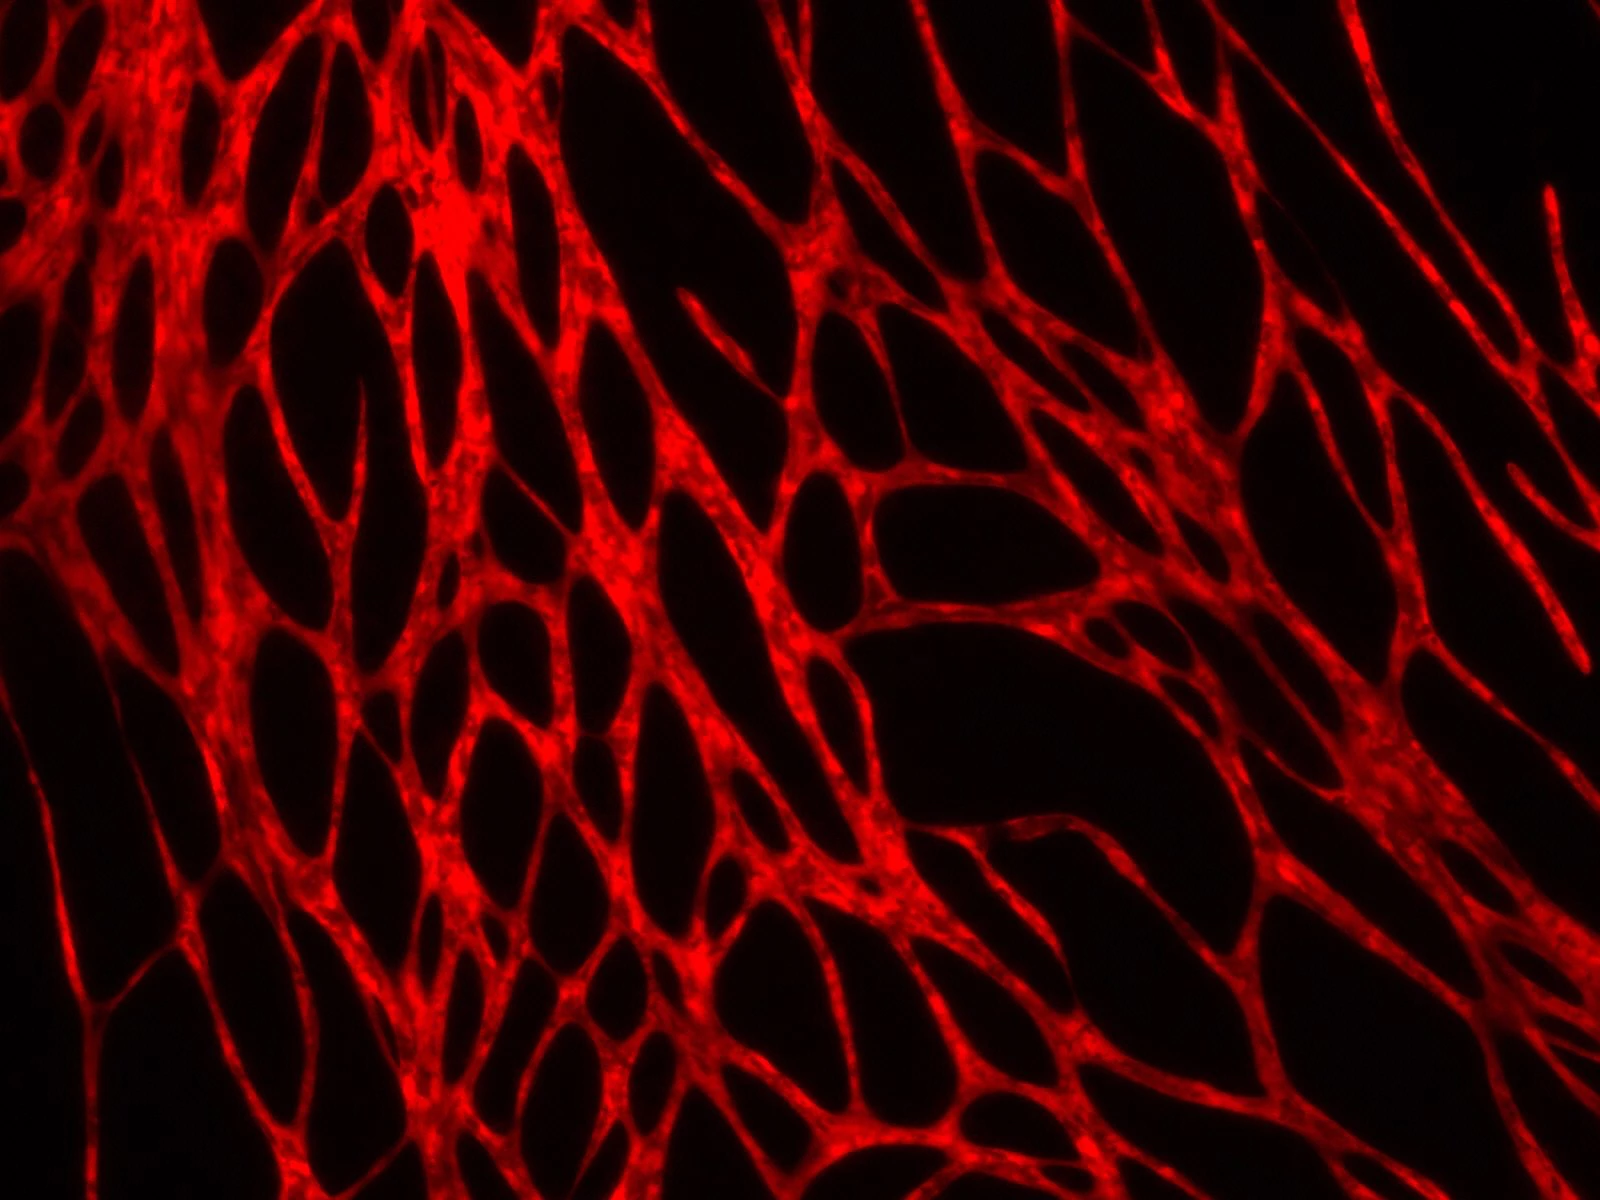

More recently, in collaboration with colleagues at Yale University, they added certain "key elements" to those bio-inks. These elements included human endothelial cells – which line the inside of blood vessels – and human pericyte cells, which wrap around the endothelial cells. These were combined with ingredients that are typically found in bioprinted skin grafts, such as animal collagen and other structural cells.

Within the space of a few weeks, blood vessels began growing in skin that had been printed from the new bio-inks. When these pieces of the skin were grafted over open wounds on mice, the animals' blood vessels began communicating with those in the bioprinted skin, causing the grafts to become perfused with blood after four weeks.